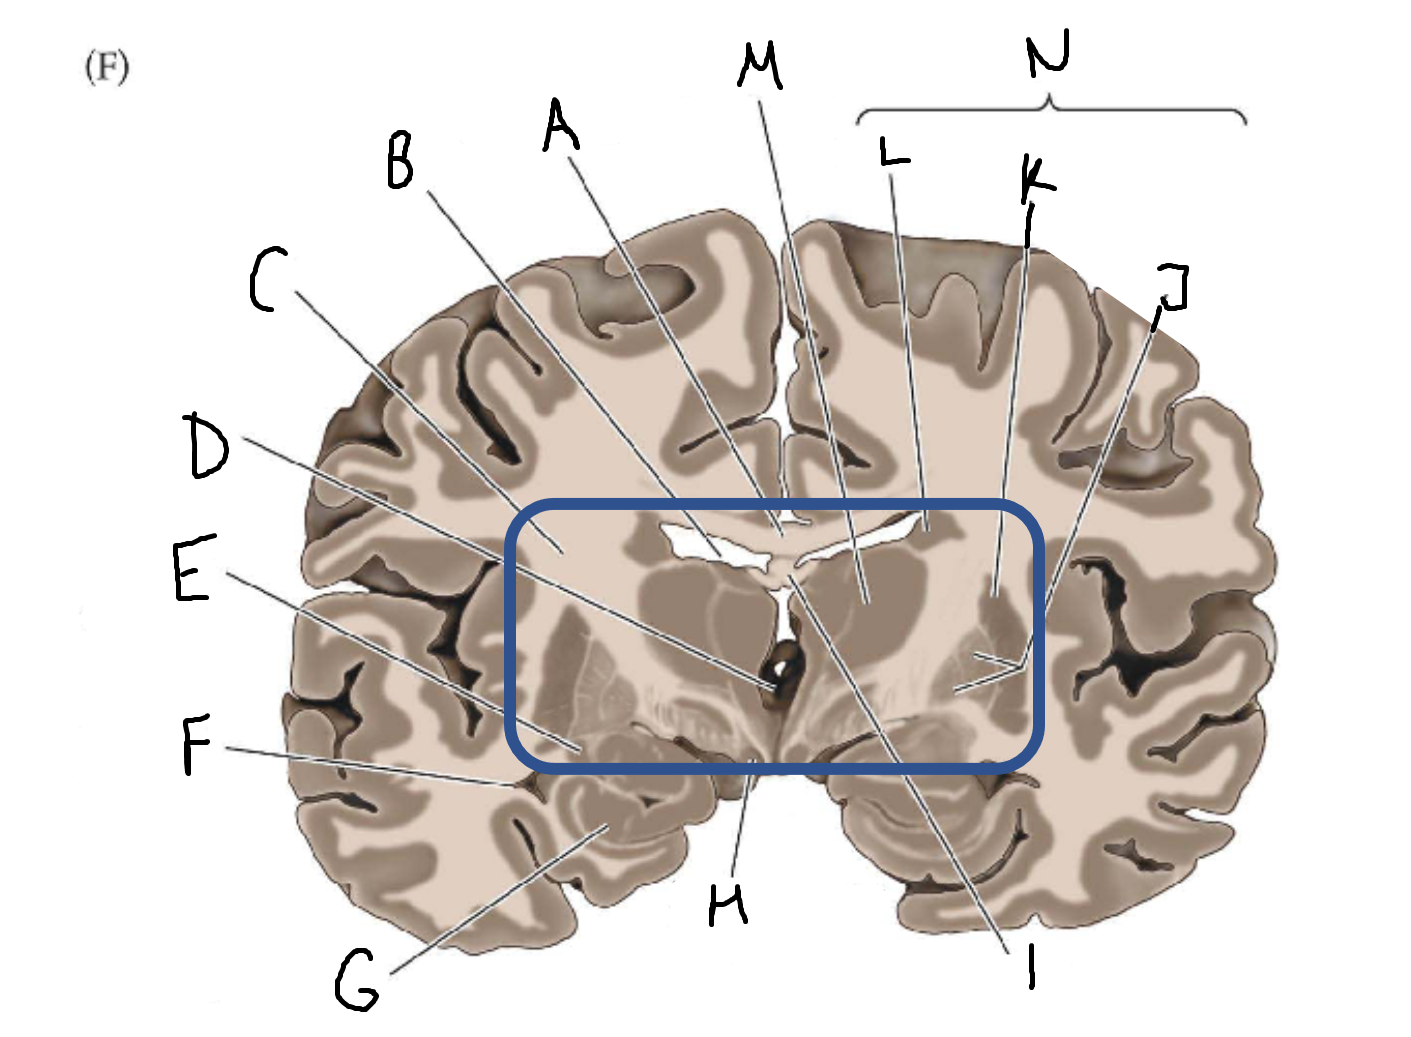

A

corpus callosum

B

lateral ventricle

C

internal capsule

D

third ventricle

E

tail of caudate nucleus

F

lateral ventricle

G

hippocampus

H

mammillary body

I

fornix

J

globus pallidus

K

putamen

L

caudate

M

thalamus

N

basal ganglia